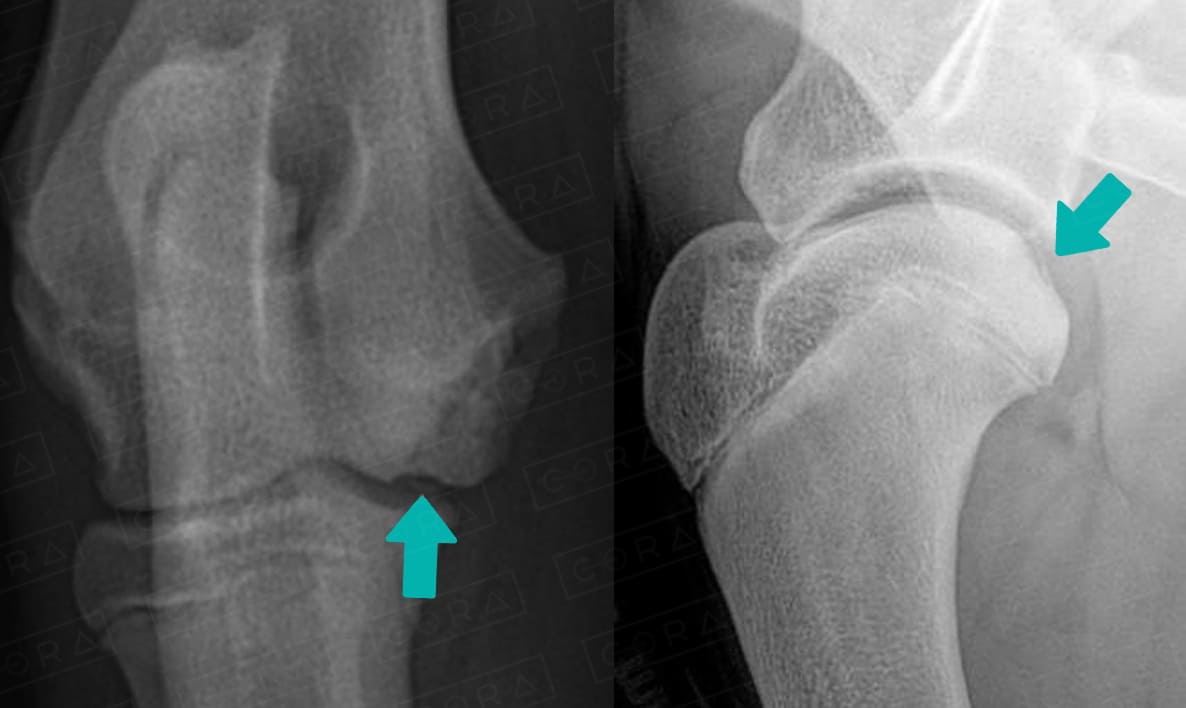

O diagnóstico é baseado nos achados

radiográficos, que, na maioria dos casos, são suficientes

para fechar o diagnóstico. No entanto, em

alguns animais é necessário a realização da tomografia computadorizada.